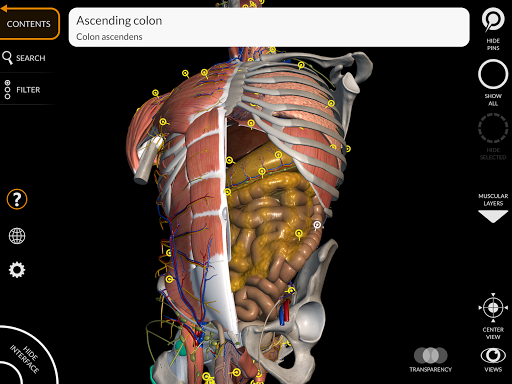

"Anatomy 3D Atlas" memungkinkan Anda mempelajari anatomi manusia dengan cara yang mudah dan interaktif.

Melalui antarmuka yang sederhana dan intuitif, Anda dapat mengamati setiap struktur anatomi dari sudut mana pun.

Model 3D anatomi sangat terperinci dan memiliki tekstur hingga resolusi 4k.

Pembagian berdasarkan wilayah dan tampilan yang telah ditetapkan sebelumnya memudahkan pengamatan dan studi bagian tunggal atau kelompok sistem dan hubungan antara organ yang berbeda.

saraf • Sistem pernapasan • Sistem pencernaan • Sistem urogenital (pria dan wanita) • Sistem endokrin • Sistem limfatik • Sistem mata dan telinga FITUR • Antarmuka yang sederhana dan intuitif • Putar dan perbesar setiap model dalam ruang 3D • Opsi untuk menyembunyikan atau mengisolasi satu atau beberapa model yang dipilih • Filter untuk menyembunyikan atau menampilkan setiap sistem • Fungsi pencarian untuk menemukan setiap bagian anatomi dengan mudah • Fungsi penanda untuk menyimpan tampilan khusus • Rotasi cerdas yang menggerakkan pusat rotasi secara otomatis • Fungsi transparansi • Visualisasi otot melalui tingkat lapisan dari yang superfisial hingga yang terdalam • Dengan memilih model atau pin, istilah anatomi terkait akan muncul • Deskripsi otot: asal, • Tampilkan/ Sembunyikan antarmuka UI (sangat berguna dengan layar kecil) MULTIBAHASA • Istilah anatomi dan antarmuka pengguna tersedia dalam 11 bahasa: Latin, Inggris, Prancis, Jerman, Italia, Portugis, Turki, Rusia, Spanyol, Mandarin, Jepang, dan Korea • Istilah anatomi dapat ditampilkan dalam dua bahasa secara bersamaan PERSYARATAN SISTEM • Android 8.0 atau yang lebih baru, perangkat dengan RAM minimal 3GB Reversi

• Sistem pencernaan